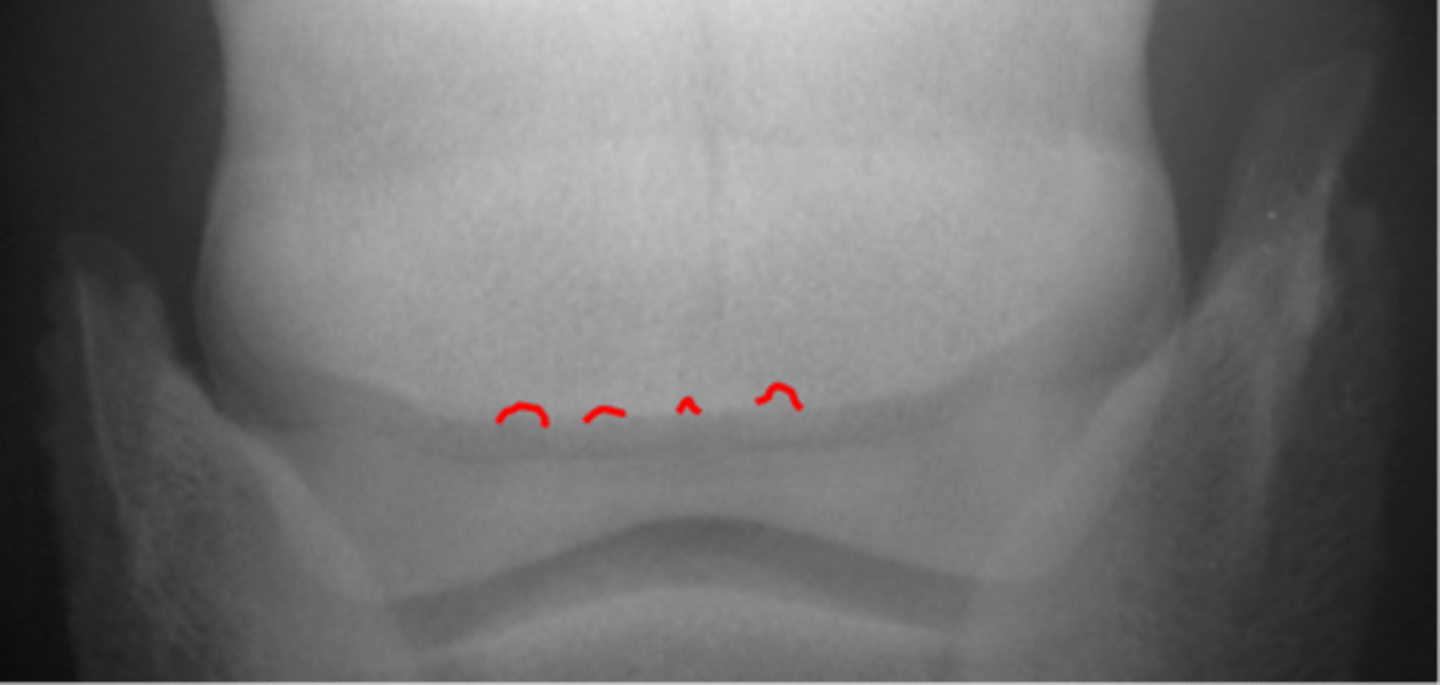

Synovial invaginations

Flexor skyline

What view is this?

1. Flexor surface

2. Corticomedullary distinction

3. Number of synovial invaginations

What is the flexor skyline used to evaluate?

Synovial invaginations